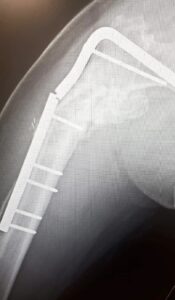

- Work got feverish then we all went to Amsterdam. I gave a ‘burst’ (4 minute talk) on 1-3-10-30 and hung around a stand with it on to talk to people about it. At some point in the next 24 hours my leg re-broke (but I thought I’d just pulled muscles)

- Spent most of the month in pain and working from home. At the end of the month went for an x-ray where they confirmed the leg was broke again.

- Had a bunch of scans, tests and negotiated with an anaesthetist so that I could have surgery at the end of the month. Did that surgery.

- VV’s birthday. Lots of Peppa pig. Me attempting to be in convalescence but back to where we were at the start of this post. Scans look good apparently but the consultant says ‘hope’ a lot.